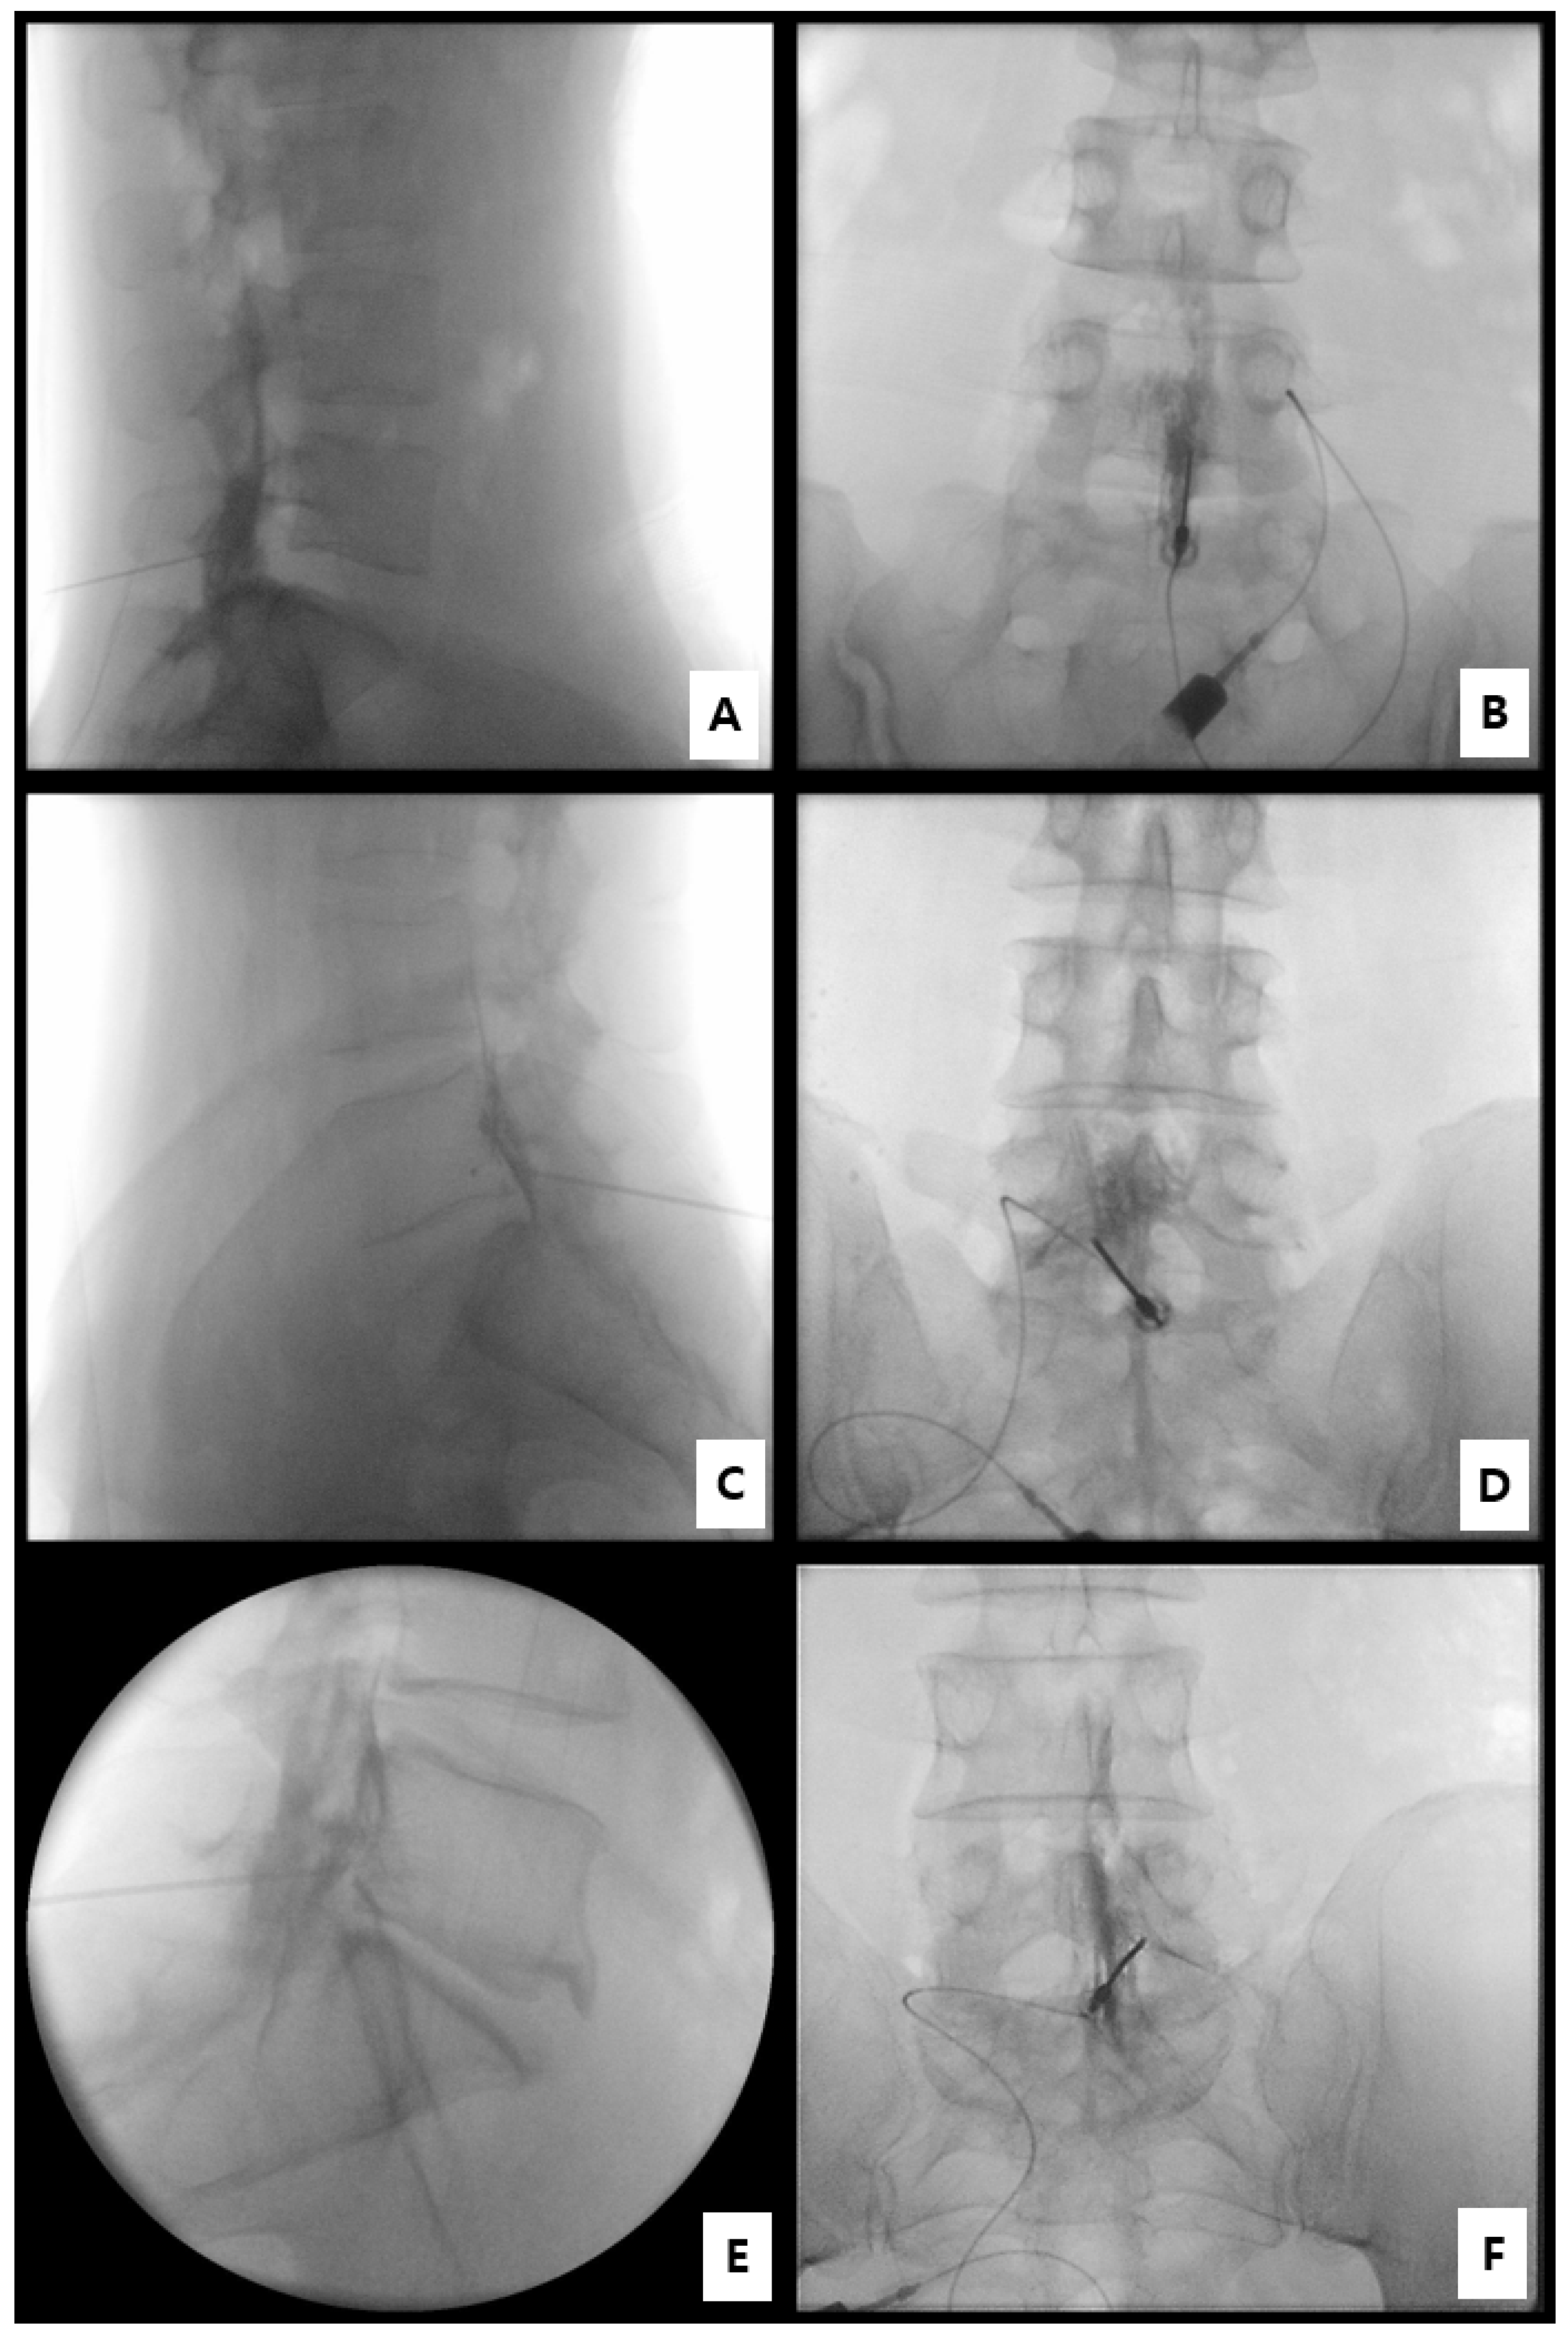

2.3. Procedural Technique for Catheter-Free LIVEI at L5–S1

- Step 1. Fluoroscopic target identification (AP)

- Step 2. Midline entry and bone docking

- Step 3. Interlaminar epidural access confirmation

- Step 4. Controlled ventral advancement (“saline cushion” technique)

- Step 5. Fluoroscopic confirmation of ventral epidural positioning

- Step 6. Final injectate delivery